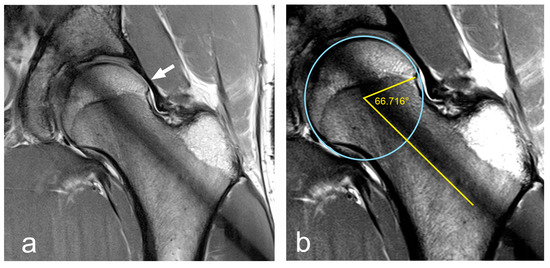

- Irregularity at the femoral head–neck junction.

- Alpha angle > 60°.